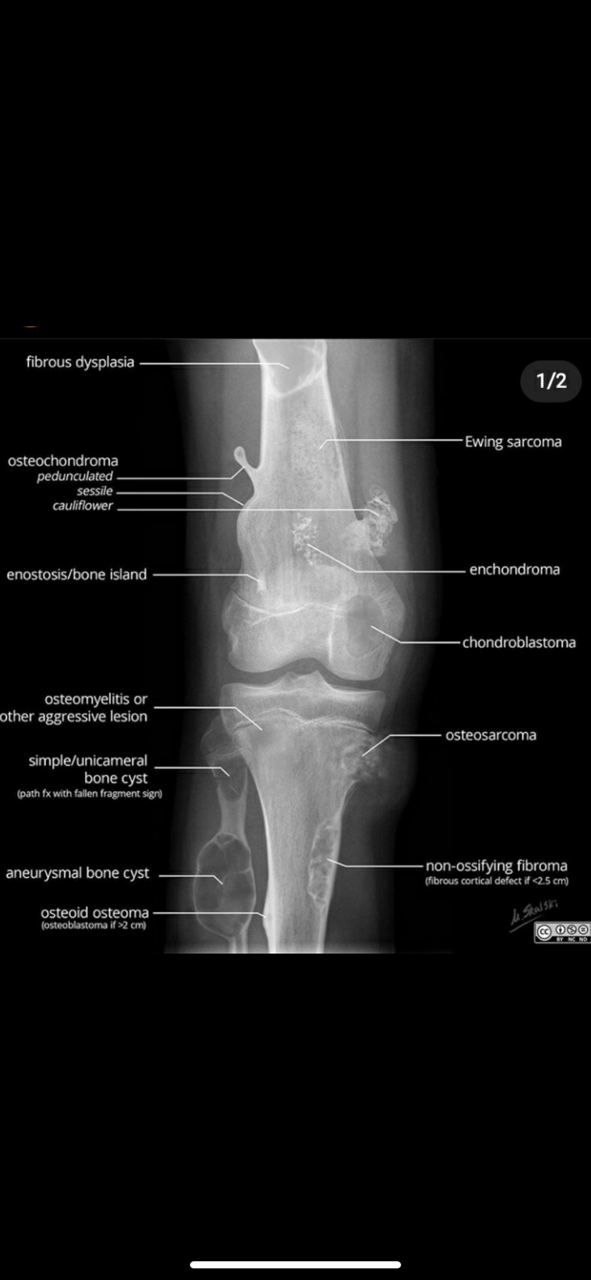

АБ

Ребенок 2004 гр

Дз

Аневризматическая киста

Не

Это ОБК

Доброкачественные опухоли

Откуда такая уверенность ? ОБК  в таком  возрасте казуистика. Полностью согласен с аневризмальной кистой

+ я тоже за АКК. В костных очагах,  когда рентген морфология идентична, значимы критерии: возраст и локализация. Менее 20 лет и дистальный эпиметафиз большеберцовой говорят больше за АКК. Хотя насколько это важно? Оба варианта доброкачественные, тем более ОБК часто сосуществует с АКК